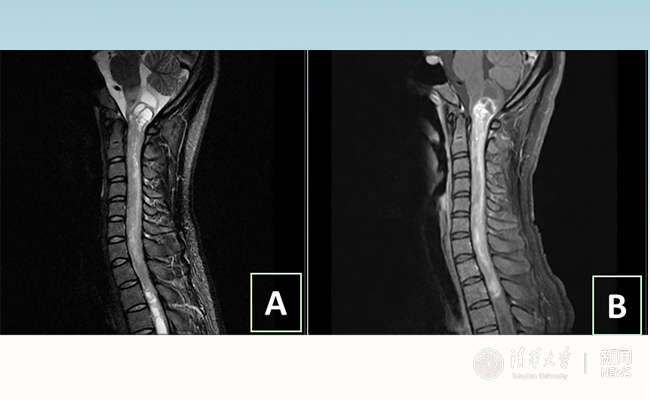

2018.01拯救“90后”女孩 清华长庚神经外科切除20多公分髓内肿瘤

“愿得韶华刹那,开得满树芳华。”27岁的患者小甜(化名)在心博在线登录入口附属北京清华长庚医院成功进行了手术,神经外科主任王贵怀为其切除了自延髓至胸髓的长达20余公分的脊髓内肿瘤。1月9日,小甜顺利出院,再续芳华!